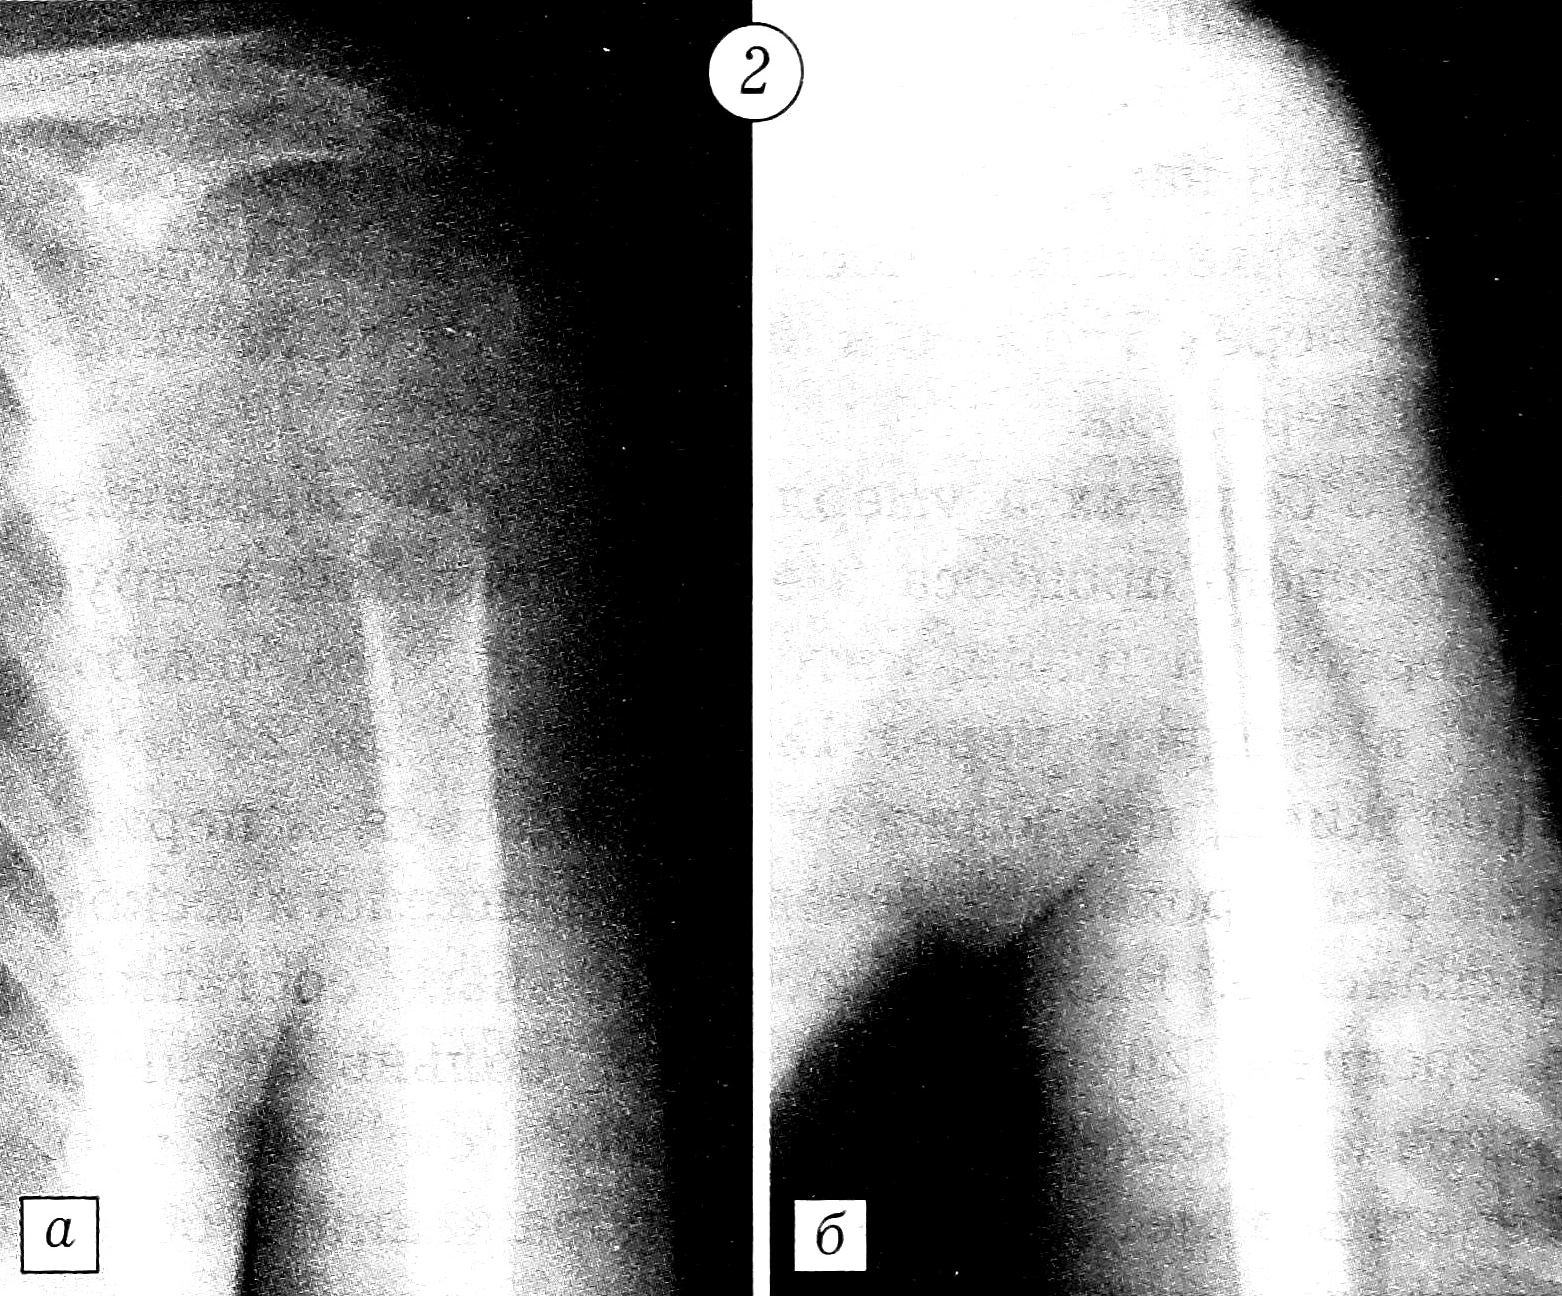

Фиксация отломков выполнялась по методике АО с применением металлоконструкций в комбинации с заполнением костного дефекта цементом [3, 5, 6]. Больной с обширным остеолитическим поражением проксимального отдела бедра произведено эндопротезирование. Поскольку ацетабулярный компонент тазобедренного сустава не был вовлечен в опухолевый процесс, выбран метод тотального эндопротезирования по Вирабову. Такая тактика снижает риск развития нестабильности сустава и необходимость повторных реконструктивных операций. При переломе диафиза плечевой кости отломки были фиксированы аппаратом Илизарова. У больного с патологическим переломом лучевой кости на фоне деструктивного остеолитического поражения, захватывающего ее дистальные 2/3, выполнена резекция патологического очага с последующим созданием синостоза культей лучевой кости с локтевой костью и артродезированием кистевого сустава длинной компрессионной пластиной АО (рис. 1). Больной с патологическим переломом головки и шейки плечевой кости после радикальной резекции метастатического остеолитического очага произведено эндопротезирование проксимального отдела плеча протезом из акрилоксида по Воронцову (рис. 2). При подвертельном переломе и переломах диафиза и шейки бедра после радикального удаления метастаза выполняли стабилизацию отломков Г-образными пластинами и конструкциями DHS с последующим заполнением образовавшегося дефекта костным цементом. В комбинации с компонентами стабилизирующих конструкций костный цемент повышает прочность фиксации (рис. 3 и 4).

Рис. 4. Рентгенограммы левой бедренной кости больной с подвертельным переломом в области метастаза рака молочной железы. a — до операции; б — после остеосинтеза конструкцией DHS.